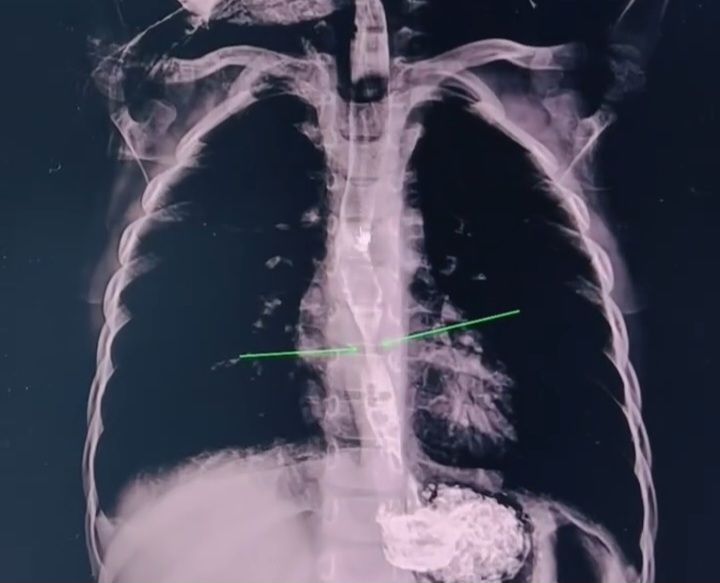

Bakıda 2 yaşlı uşaq yağ çözücü məhlul içib.

Medicina.az xəbər verir ki, bu barədə tanınmış radioloq Aydın Əliyev bildirib.

Uşağın rentgen görüntülərini paylaşan həkim valideynlərə xəbərdarlıq edib.